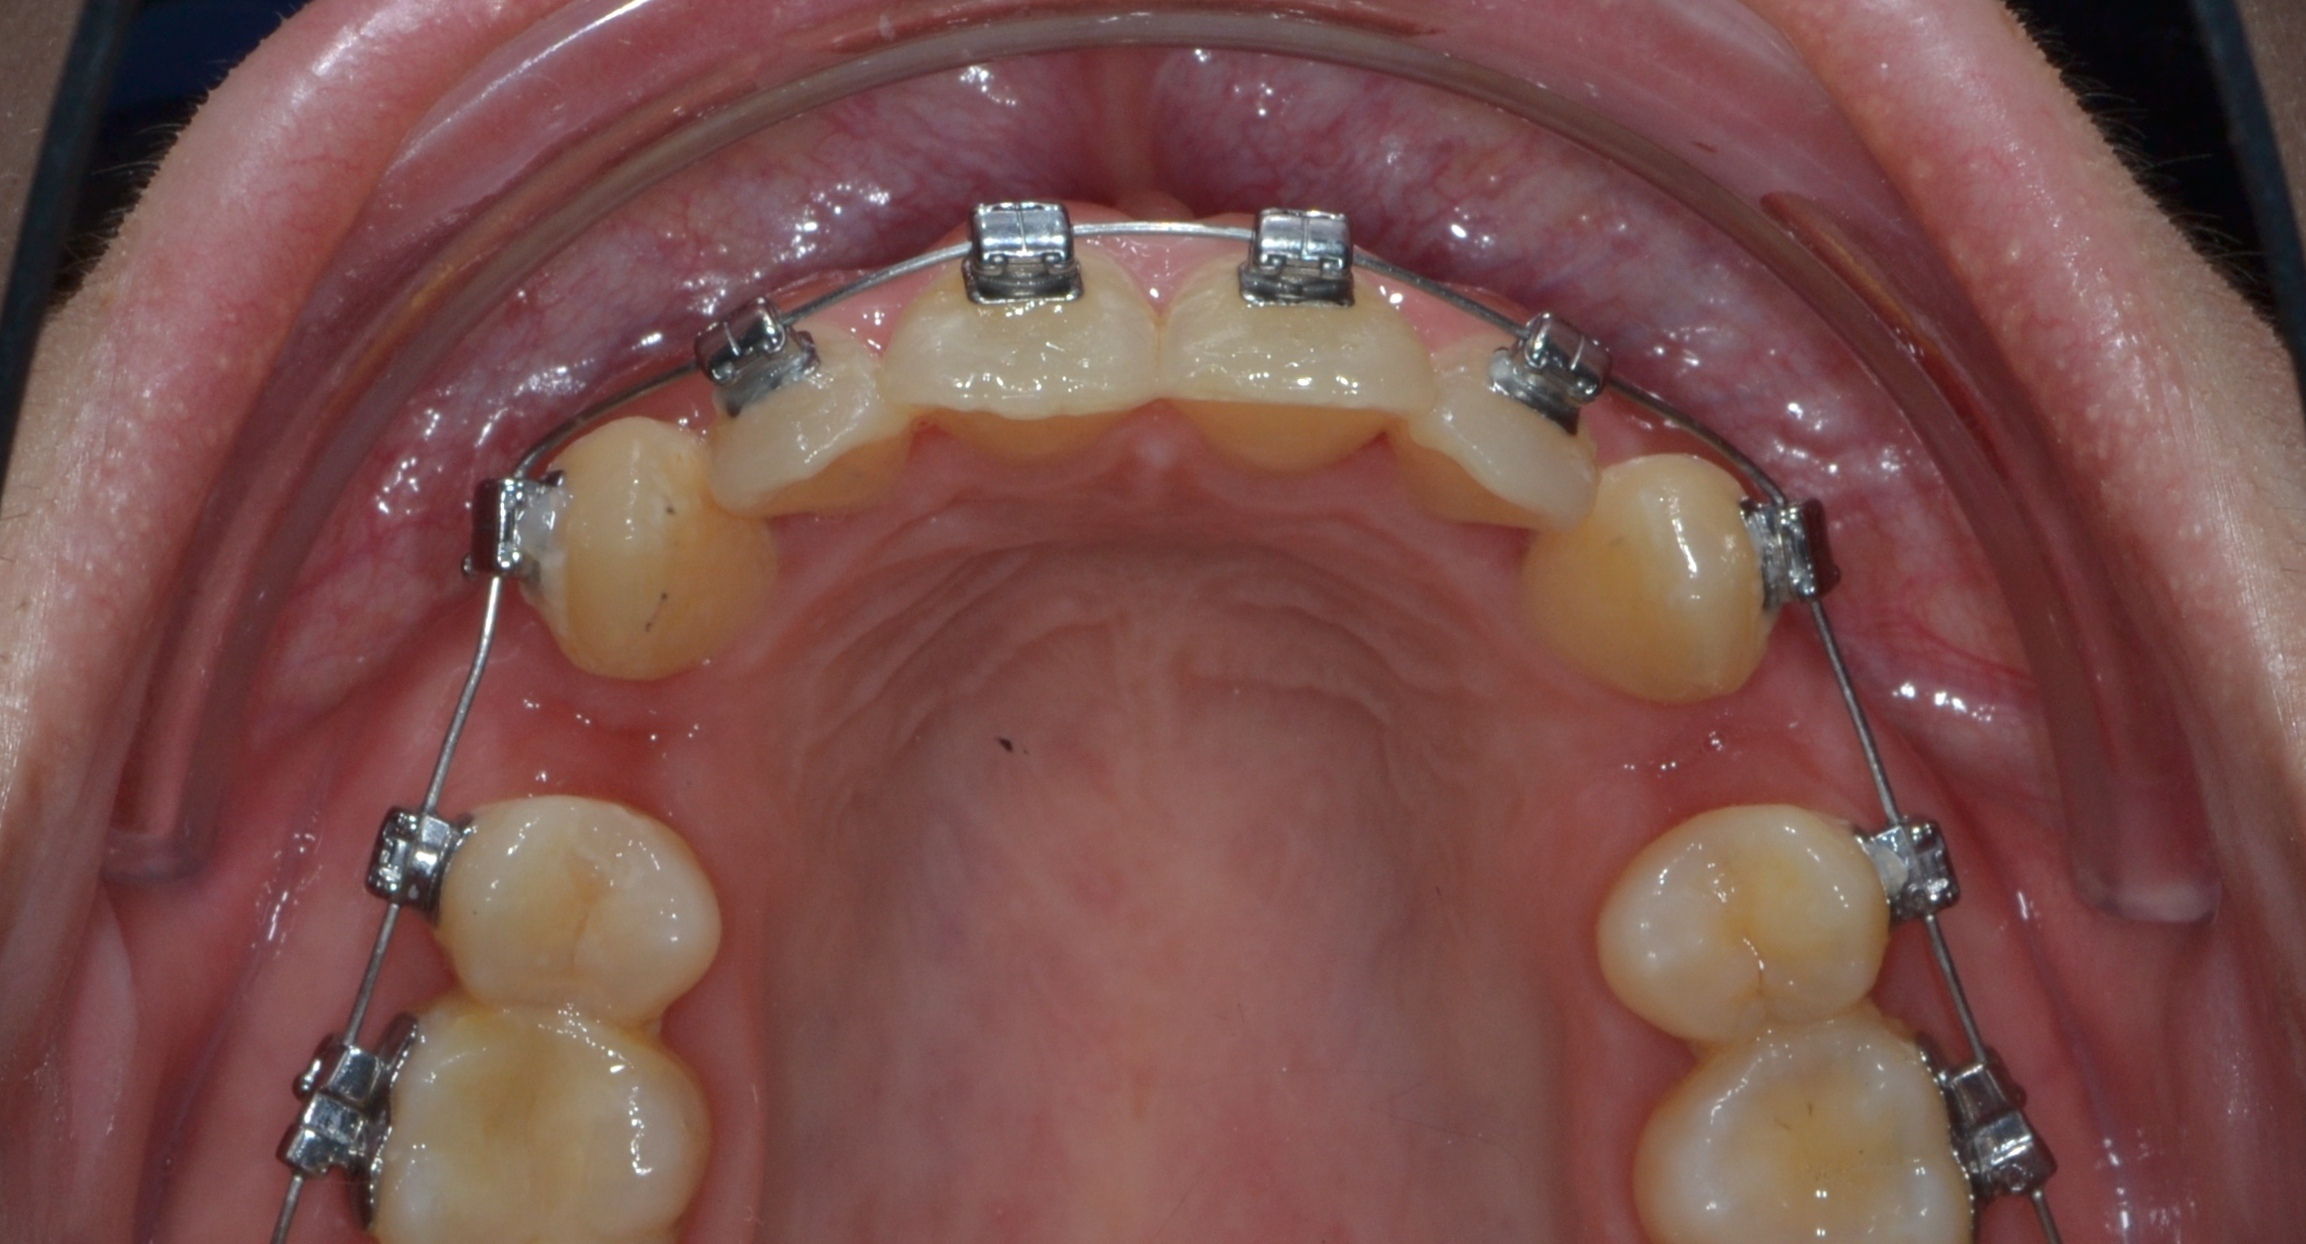

До фиксации

Декабрь 2024 г.

2

1.5 месяца

Частичная ретракция премоляров и клыков 1.5 мм